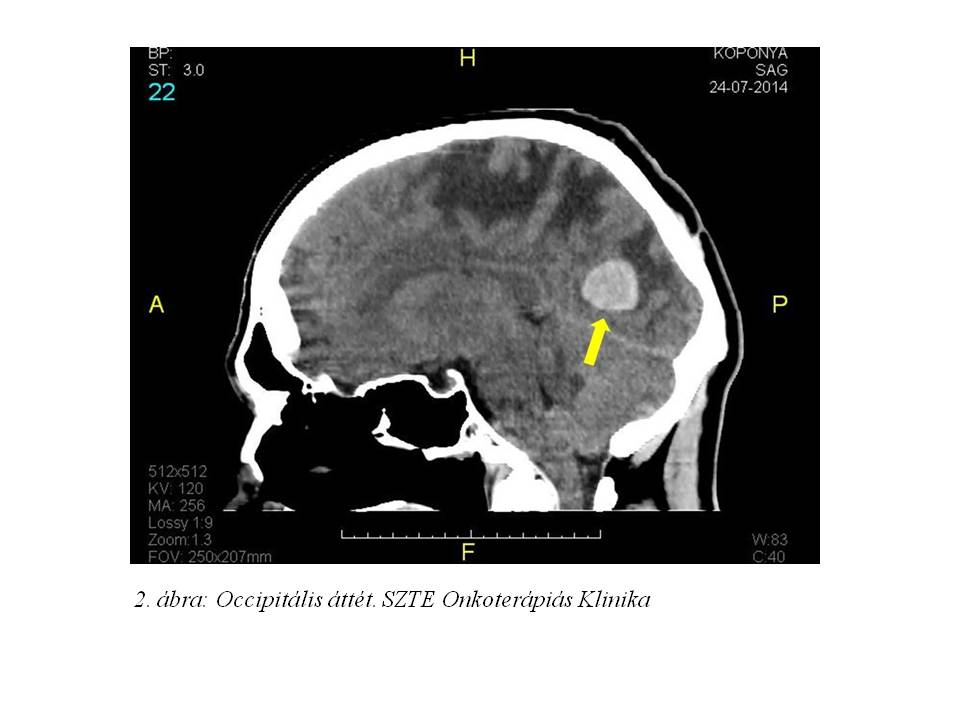

Egy 56 éves férfi betegünk kórtörténetét mutatom be, akit az SBO-ról vettünk át osztályunkra fejfájást, szédülést, hányingert és hányás okozó ismeretlen primer tumor multiplex agyi áttéteinek palliatív irradiaciójára (1. ábra, 2 ábra).

A kezelés megkezdése előtt kontroll koponya CT vizsgálat készült, mely a korábbi multiplex gócoknál regressziót véleményezett (7. ábra, 8. ábra).